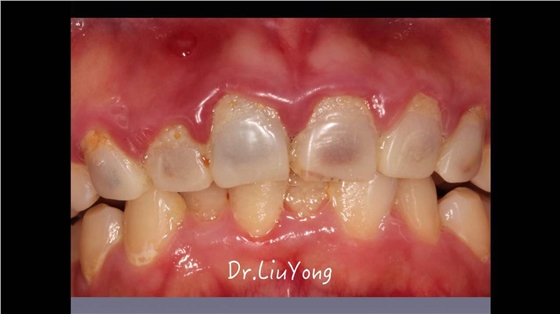

嚴重破壞生物學寬度,根尖瘺管,重行根管治療,第一次冠延長建立唇腭側及鄰面BW, 術后牙齦扇貝形差,齦乳頭黑三角,再次行美學冠延長,建立牙齦扇貝形,手術免費, 患者因經濟原因只能選擇鑄樁及鈷鉻合金烤瓷冠。終于完工